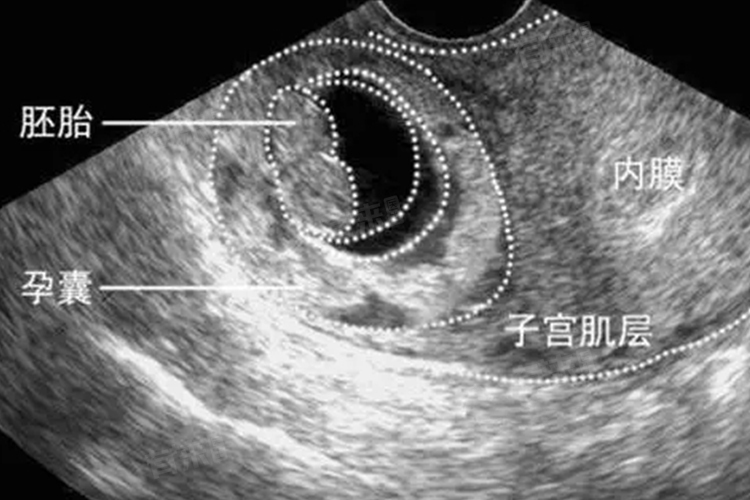

1、怀孕5周:女性怀孕约5周时,通过经阴道超声检查,可能会看到孕囊,在这个阶段,孕囊通常较小,直径可能在几毫米到1厘米之间,正常情况下,孕囊应位于子宫腔内,呈圆形或椭圆形,胚胎的发育刚刚开始,孕囊内可能还看不到明显的胎芽和胎心搏动,但这已经为后续胚胎的正常生长奠定了基础。

2、怀孕6周:到了怀孕6周,孕囊会更加清晰可见,直径通常会有所增大,可能达到1-2厘米,通过超声检查,不仅能看到孕囊,还有较大可能观察到胎芽的出现,胎芽是胚胎早期的形态,标志着胚胎发育的进一步进展,部分孕妇在这个时期也能检测到微弱的原始心管搏动。

3、怀孕7周及以后:怀孕7周及之后,孕囊的形态和结构会更加完善,孕囊直径一般会超过2厘米,胎芽也会更加明显,长度逐渐增加,在这个阶段胎心搏动会清晰可测,是判断胚胎存活和健康发育的重要指标,如果此时仍未看到孕囊、胎芽或胎心,可能需要进一步检查以排除胚胎发育异常或异位妊娠等情况。